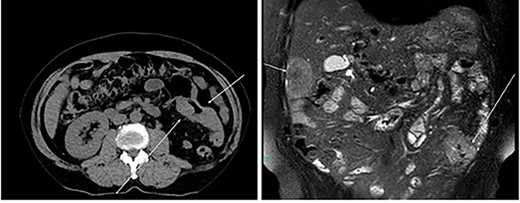

An otherwise healthy 73-year-old male, presented with rectal bleeding 6 months back. Colonoscopy revealed a sigmoid colon mass about 25 cm from the anal verge extending 10 cm proximally and a biopsy confirmed invasive adenocarcinoma (Fig. 1) Computed tomography of the abdomen and pelvis revealed a circumferential wall thickening involving the distal colon/proximal sigmoid colon spanning for 6 cm with maximum thickness of 2.3 cm, and it was also associated with surrounding fat stranding and multiple regional lymph nodes. Liver lesions were described as ill-defined hypodense lesions in two segments. The first lesion was seen in segment 7 measuring 6 × 7.5 cm and the other was seen in segment 5 measuring 6 × 3 cm (Fig. 2). Furthermore, chest CT showed no lung metastasis and a carcinoembryonic antigen level of 24.8. Eventually, a diagnosis of metastatic sigmoid adenocarcinoma with liver lesions was made. The multidisciplinary team decided to start the patient on Nac and then the case was reassessed for further resection. After completing five cycles FOLFOX, a CT of chest, abdomen and pelvis was performed for evaluating the response. The primary descending colon tumor demonstrated reduction in bulk with persistent serosal irregularity and no definitive regional lymphadenopathy was detected. The hepatic lesions revealed a partial response; in segment 7, the lesion is currently measuring 3.9 cm and in segment 5, the lesion measures 2.7 cm. Partial response to therapy was noted by a 41% reduction in sum tumor burden as per RECIST criteria (Fig. 3). The clinical tumor node metastasis classification post chemo was calculated to be T2N0M1 for descending colon cancer along with a CEA of <1.7. Despite not adding a biological agent with the systemic therapy which is the standard protocol in metastatic CRC, the patient achieved a remarkable reduction in tumor burden. The patient underwent a laparotomy with a low anterior resection of the rectum and anastomosis, synchronous resection of segments 6 and 8 of the liver along with a right-sided diaphragmatic stripping.